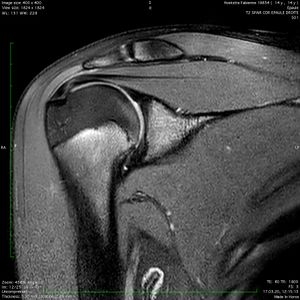

Full or partial thickness tears or avulsions suggestive of an accident are to be distinguished from degenerative tears, which consist rather in tendon thinning or tendon stump shortening.[8][9] These tendinopathy-associated defects, as well as occupational diseases, will not be dealt with here (please refer to https://wiki.beemed.com/view/Shoulder:Rotator_Cuff_Pathology/Rotator_Cuff_Tendinopathy), being degenerative rather than accidental in nature. Partial thickness lesions may be as well of traumatic origin,[10] even in very young subjects (Figure).[11]

Magnetic resonance imaging of a 14-year-old patient after a ski fall. Observe the 10 mm long interstitial tear.